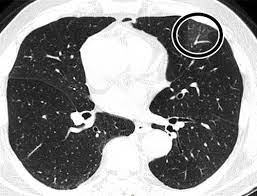

Diagnostic Accuracy Of North America Expert Consensus Statement On Reporting Ct Findings In Patients Suspected Of Having Covid 19 Infection An Italian Single Center Experience Radiology Cardiothoracic Imaging

Diagnostic Accuracy Of North America Expert Consensus Statement On Reporting Ct Findings In Patients Suspected Of Having Covid 19 Infection An Italian Single Center Experience Radiology Cardiothoracic Imaging from pubs.rsna.org